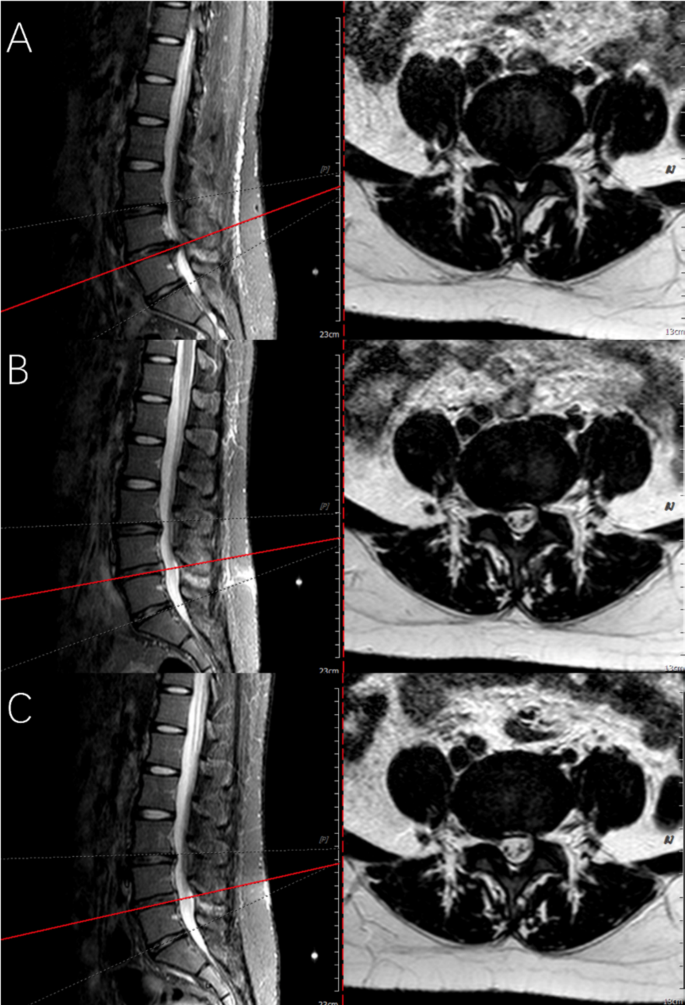

Compared with that before the operation, the height of intervertebral space decreased 1 year after the operation, but the difference was not statistically significant (P = 0.070). No significant difference between the preoperative and postoperative Pfirrmann grade of the disc was observed (P = 0.437). One case showed imaging recurrence post-operation but had no clinical symptoms and did not receive additional treatment. No reoperation cases were observed during the follow-up period. Figure 6 shows preoperative and postoperative follow-up MRI images of patients with LDH, indicating no recurrence after one year of follow-up.

Preoperative and follow-up lumbar MRIs of the patient using bone-anchor suture technique. (A) Indicates the preoperative sagittal and axial MRIs, showing L4/5 herniation with spinal cord compression. (B) To avoid the artifact signal of spinal cord edema in immediate postoperative MRI examination, MRI re-examined at three-month follow-up indicates the spinal cord and nerve root were decompressed. (C) indicates the lumbar MRIs at one-year follow-up.